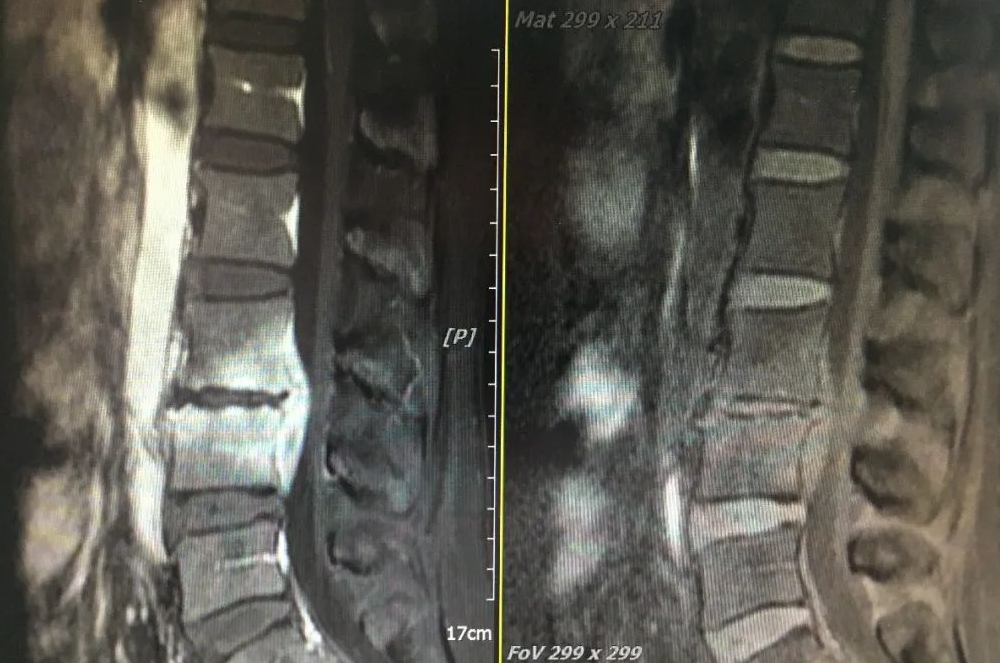

术前MRI

48岁的陈姐原本身姿挺拔,体态优美,一个月前出现持续的腰痛,到漳州市中医院就诊后发现病情远比想象的严重,经X线、CT、MRI检查回报考虑:脊柱感染(腰3-4):细菌感染?结核?布什菌感染?完善炎症及结核特异性检查,也未能明确感染原因,这给治疗用药带来很大困难。